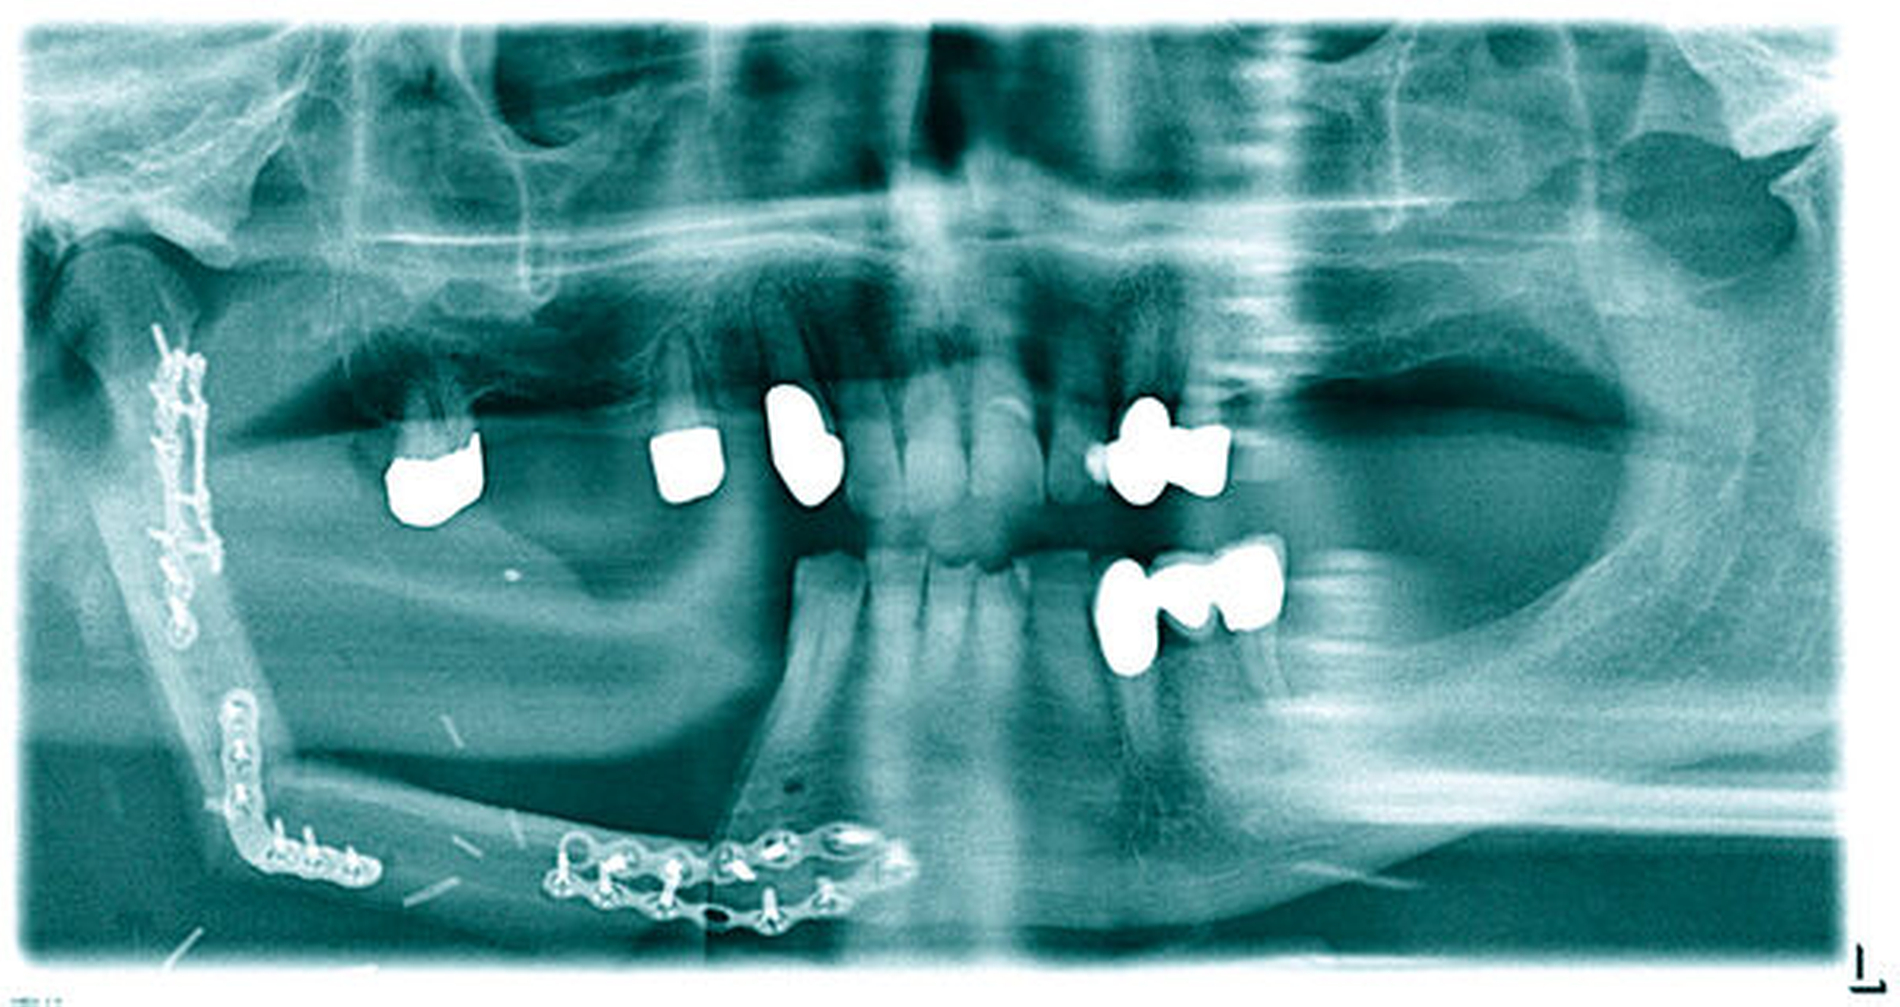

Die ablschießende Histologie ergab die In-sano-Resektion des PEC ohne nachweisbaren Lymphknotenbefall [pT2, pN0 (0/19), L0, V0, Pn0, G1, R0] (UICC, 8. Auflage). Das postoperativ angefertigte Orthopantomogramm dokumentiert die Rekonstruktion des Unterkiefers mit dem eingebrachten zweisegmentalen Fibulatransplantat und dessen Fixierung mit Osteo-synthesematerial (Abbildung 8).